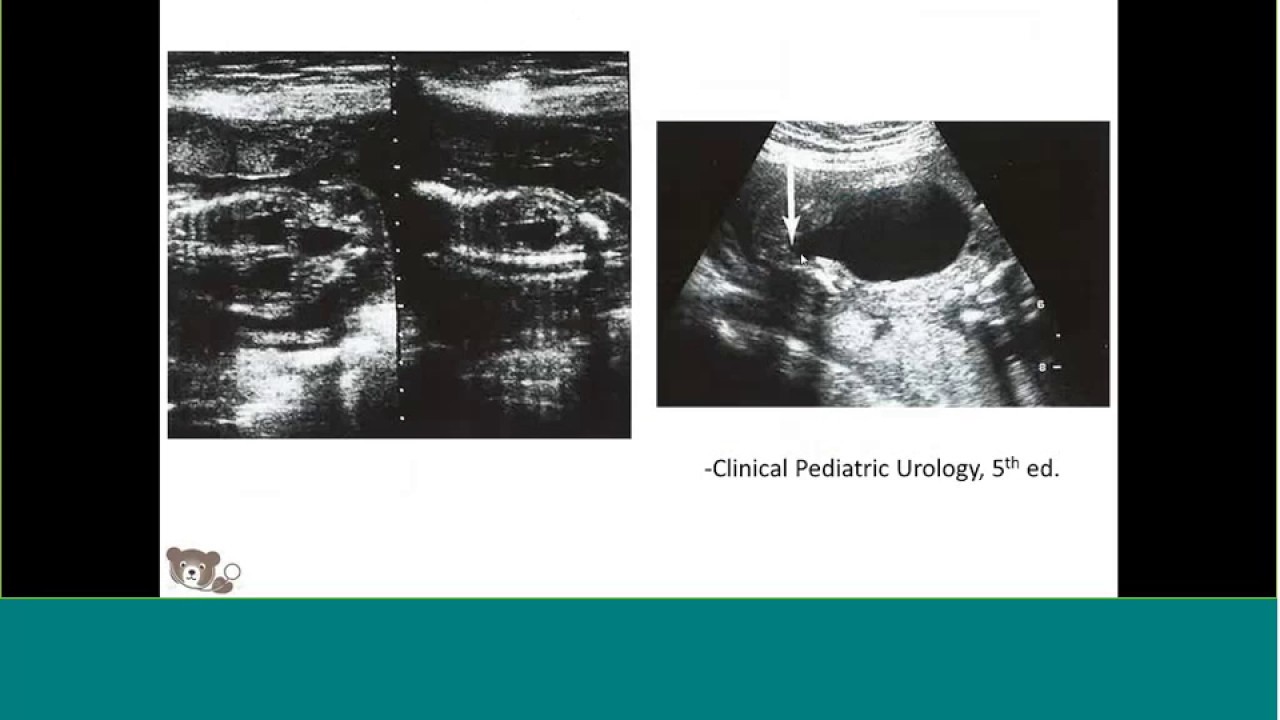

Fetal Hydronephrosis